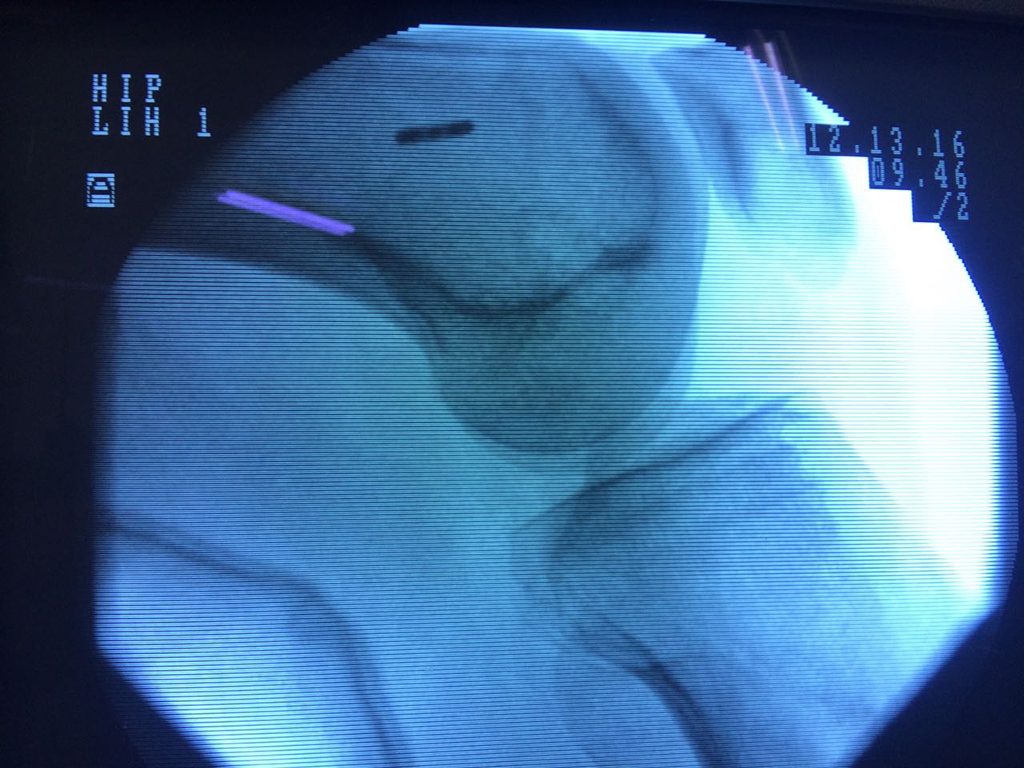

Cirugía de Rodillas